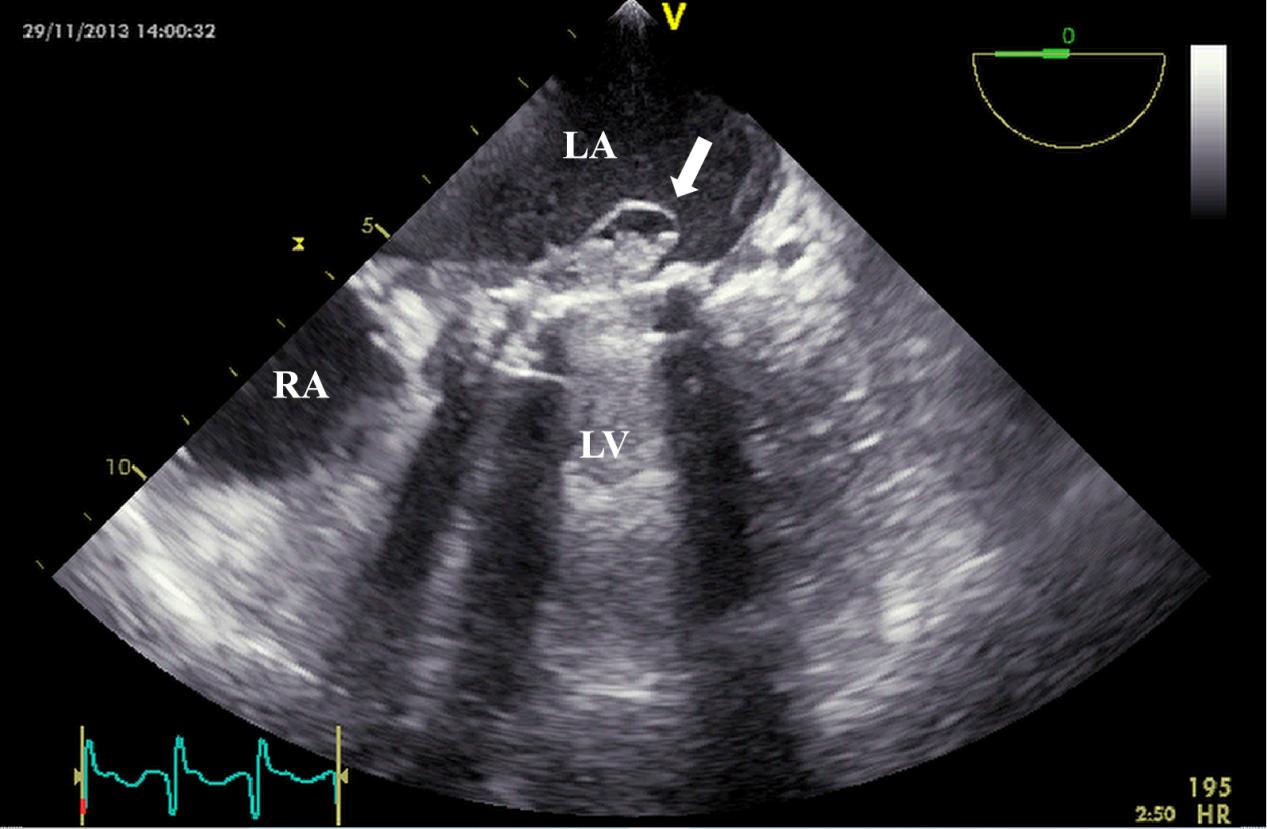

Echocardiography is the preferred imaging diagnostic modality for PVE, which can effectively identify valvular lesions and peri-valvular complications, such as abscesses, dehiscence, and paravalvular infections (Figs. 5,6,7). In the early postoperative period, attention should be paid to possible anatomical variations, such as edema-related changes, which may mimic pathological findings [23]. TEE is superior to TTE in terms of sensitivity (91% vs 65%), and its advantage mainly lies in being less susceptible to the interference of prosthetic valve artifacts. Among patients with suspected PVE, the NPV of TTE and TEE were both relatively high, ranging from 86% to 94% [9]. Furthermore, compared with two-dimensional (2D) TEE, 3D TEE can provide more comprehensive images of cardiac structures and has higher diagnostic value in the analysis of valvular lesions [46].

Fig. 7. TEE detection of mechanical valve abscess. TEE mid-esophageal view suggests mitral valve mechanical valve abscess formation (white arrow). TEE, transesophageal echocardiography; RA, right atrium.